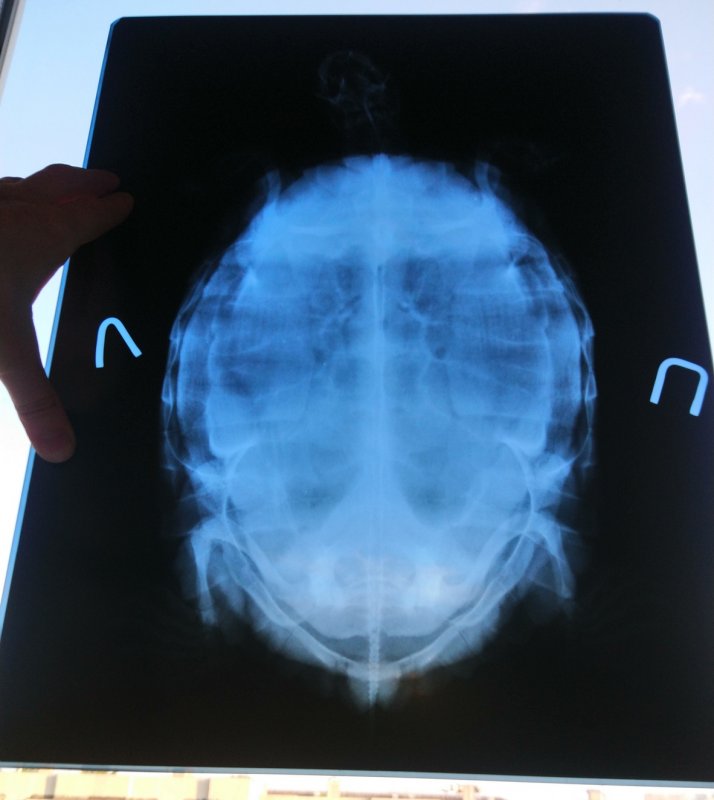

NataLiRED Ваше имя: Наталья Локация: Арзамас, РФ Опубликовано: 13 июля 2021 Автор Опубликовано: 13 июля 2021 Вернулись с рентгена. Яиц вроде не видно. Сделали ей там три снимка. Первый - обзорный с расстояния 90 см, 50 кВ на 10 мА\с. Два других - с расстояния меньше (не уверена в см), 50 и 55 кВ / 15 мА\с. Взвесились там. И все так и есть. Вес 3,05 кг. Возможно давнее взвешивание в мешке было так себе в плане точности. Борглюконат кальция и Элеовит куплены.

Консультанты moth Ваше имя: Мария Локация: Москва Опубликовано: 14 июля 2021 Консультанты Опубликовано: 14 июля 2021 @NataLiRED в соседней теме была похожая ситуация, там у черепахи в итоге оказалась пневмония, именно поэтому я советую брать хотя бы онлайн консультацию, но именно у врача-герпетолога. Т.к. мы тут не врачи и даём рекомендации на основе статистики и симптомов, а в реальности всё может быть не так. Тем более, что яиц у неё нет. Я могу расписать Вам схему кальция и Элеовита, но тут может быть дело в другом. 300р не такая большая сумма, подумайте о консультации. Врач консультирует в своём телеграмм канале, Вам нужно написать свой ник и я Вас добавлю, там уже будете общаться непосредственно с герпетологом. Для диагностики потребуются снимки в других проекциях, чтобы посмотреть лёгкие, но это уже врач Вам всё расскажет. Если не хотите брать платную консультацию - скажите, я распишу тогда схему кальция.